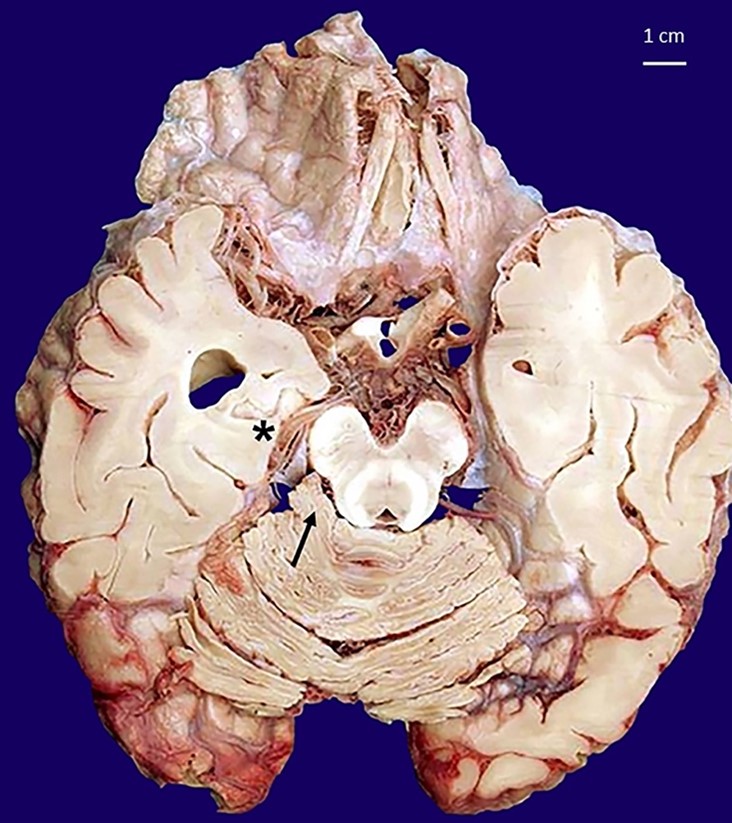

A 26-year-old girl was found dead in her home. Her family members reported they had seen her alive a few hours before and that she occasionally suffered from migraine, which was never medically investigated and treated with over-the-counter analgesics. They declined alcohol or drug abuse. The autopsy was ordered by the Judicial Authority. At post-mortem examination, the corpse was in good preservation conditions (weight = 52 kg, length = 171 cm). It did not present any sign of traumatic-blunt lesion on external examination. At cadaveric dissection, the brain showed smoothed convolutions and shallower grooves than normally and there was evidence of supratentorial herniation (uncal right) with tonsillar imprint (Figure 1). In the right cerebellopontine subarachnoid area, there was an unencapsulated neoformation in 0.8 cm in diameter with a well-delimited surface of yellowish color and elastic consistency (Figure 2). Nothing else significant emerged from the autopsy examination.

Toxicological analyses were negative for determining Blood Alcohol Concentration (BAC), narcotics, and psychotropic substances. On the other hand, histopathological investigations of the viscera and the cerebellopontine neoformation showed a formation composed by mature adipocytes, allowing to define it as an intracranial lipoma (Figure 3).

No evidence of malignancy was observed. Areas of acute neuronal hypoxic distress in the bulbar site (olive) and diffuse cerebral edema of a severe degree, mainly in the right hemisphere, were also documented (Figure 4).